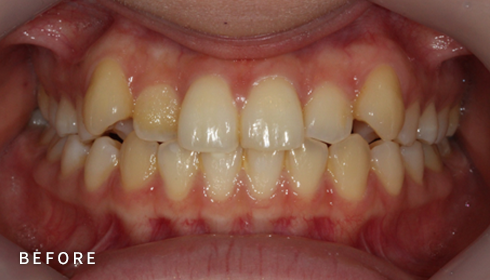

설측교정은 치아 안쪽(설측면)에 초소형 장치로 보이지 않게

아름다운 미소를 만드는 고난이도 프리미엄 교정 치료입니다.

난이도가 높은 만큼 풍부한 진료 경험이 중요합니다.

강남에서 다년간 설측교정에 특화된 경험을 바탕으로,

3D 디지털 기술을 활용한 맞춤 설계, IDBS방식을 통한

정밀하고 불편감 없는 치료를 제공합니다.